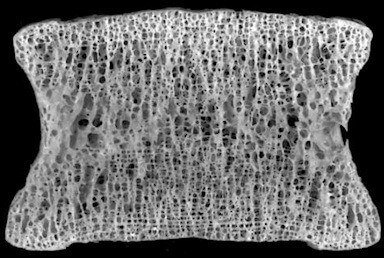

Researchers on the project suspect the diet associated with Type 2 diabetes - one high in processed fats and sugars - causes inflammation and modification of disc tissue, triggering a chain of responses, which leads to degeneration. To test this hypothesis, the researchers have set three goals: to establish whether mice fed a diet associated with Type 2 diabetes will develop intervertebral disc degeneration (IDD), isolate the effect of diet causing changes in the tissue, and evaluate how the diet modifies proteins within the disc.

At the core of the research project are the effects of advanced glycation endproducts (AGE) - proteins or lipids that have become coated in sugars, which damage their function. Research suggests that a diet high in heat-processed foods, including fried foods, plays a role in AGE formation. Research also indicates the accumulation of AGEs causes structural deterioration, increases inflammation that could lead to disc degeneration, and contributes to a host of degenerative diseases such as diabetes, atherosclerosis, and Alzheimer's.

To separate the systemic effects AGEs may have on the body from local effects in specific tissues, researchers will also look at spinal bone and disc tissue in vitro. In that research, bone and disc tissue from both normal and AGE "knock-out" mice fed on a regular diet will be bathed in a high AGE medium, accelerating the exposure of these specific tissues to AGEs. Selected tissue samples will be exposed to a drug that may be able to block AGEs in disc tissue, limiting exposure to bone and disc tissue. In all samples, the researchers will look at changes in indicators of disc and bone health such as the activity of proinflammatory cytokines and AGE formation over time. This research will separate the relative contribution of AGEs to tissue degeneration from systemic damage that may occur as a result of Type 2 diabetes-associated hyperglycemia.

Vashishth, an expert in extracellular bone matrix, has a long-term interest in investigating AGE-accumulation in bone. With his expertise, the team will also look at how changes in bone could be contributing to the degeneration of discs. Vashishth said one aspect of the feedback loop may be causing bone tissue in the spinal vertebrae to stiffen, depriving disc tissue of nutrients that would normally diffuse through the bone to the discs.